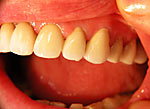

Die folgenden Patientenfälle sollen Ihnen einen Einblick in die Möglichkeiten der modernen Implantation geben.

Implantation mit fester Brücke: